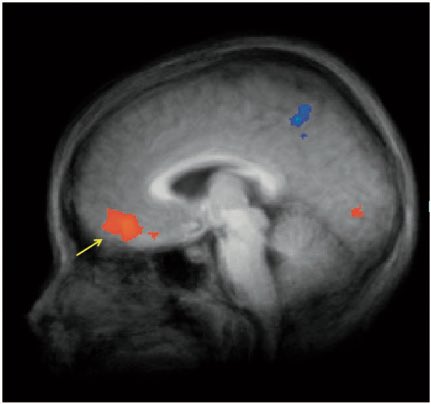

على اليمين عقل الطفل لما يعرض عليه طعام عادي، واليسار لما يعرض عليه نفس الاكل لكن بتغليف ماكدونالدز، اليمين يوضح نشاط في منطقة OFC والمرتبطة بتحديد السلوك وصنع القرار!!